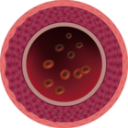

NAKON TERAPIJE

Na slici desno vidimo očišćenu desnu koronarnu arteriju već bez tragova kalcificiranog aterosklerotskog plaka kod istog pacijenta nakon 1. mjeseca terapije. Nema smrtonosnih naslaga kolesterola. Krv teče slobodno, opskrbljujući kisikom sve organe.